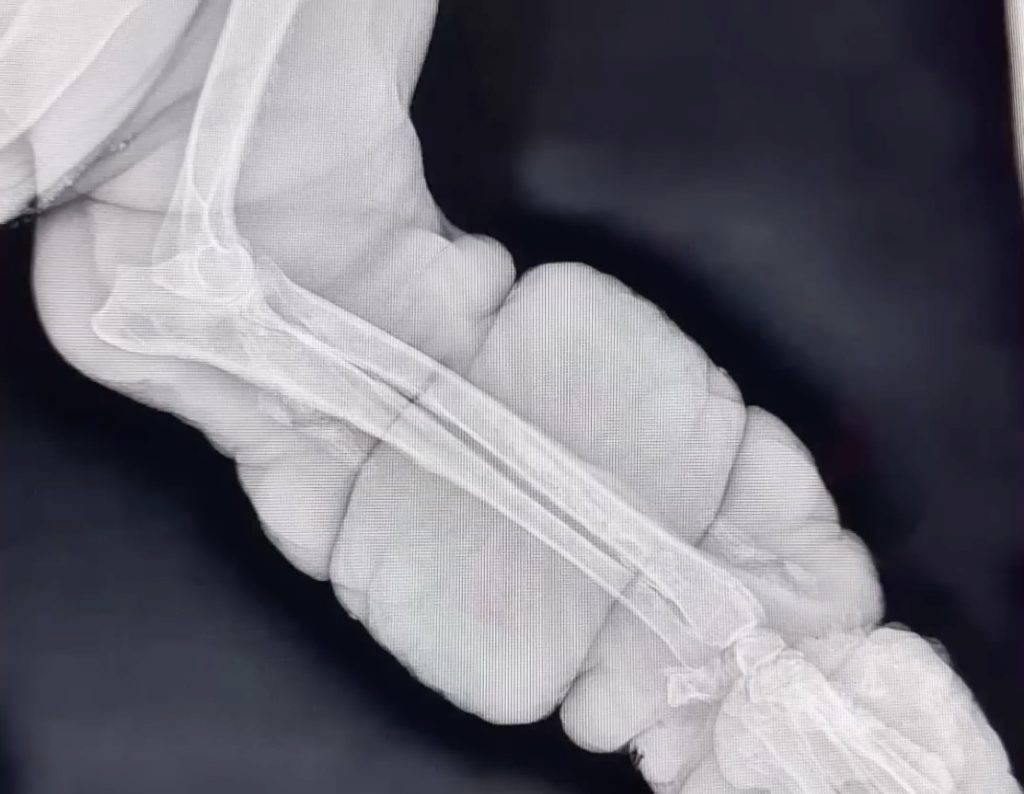

He was taken to a local animal rescue organization where volunteers gently cleaned his wounds and offered him his first real meal in days. But it was at the veterinary clinic where the full truth of his suffering came to light. After several tests and X-rays, the veterinarian delivered devastating news: Avocado had Osteosarcoma, an aggressive form of bone cancer that had taken hold in his front leg. The only way to save his life was to amputate the diseased limb.